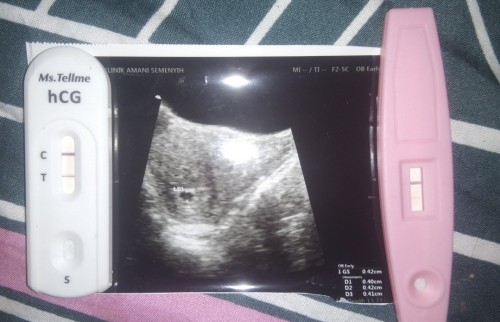

Hai saye gugur akhir bula3 tak sempat period bulan4 saye pregnant balik .. Harini pergi scan nampak kantung kecik je tapi tak tau berapa minggu doc kata mesin xdpt kire Macam mana ye nk tau berapa week sevab lepas dpt upt +ve terus saye booking n hujung mnggu depan patut buka tapi rasa takut plak sbb USOP & kantung kecik sgt #ingintahu #firstbaby #pleasehelp #firstmom #bantusharing #seriusnanya

awak sama macam sy.. sy gugur 2.1.22..preggy balik 30.1.22 sekarang da 5 bulan.🥰 memang USOD. sebabnya taktau bila last period ..sebab baru gugur kan. biasa Dr akan bagi temujanji baru untuk scan balik, untuk tengok berapa minggu and tarikh bersalin yang tepat. sy haritu macam awak la. risau kemain..sebab kantung kecik lagi..n taktau berapa minggu.. kantung makin lama makin besar, lepas scan, Dr finally dapat tarikh sebenar bersalin sy and berapa week da masa tu.. harap awak bersabar tunggu ye.. in Sha Allah baby membesar dgn sihat..n akan tau berapa weeks awak tu nanti. doakan juga baby sy sihat ye🥰

Sy pon mcm ni.. Dr anggarkan 3 or 4 mggu.. Kalau ikut 5 mggu masa tu.. Mula2 x nmpk dah suspek luar rahim.. Pergi spital tvs baru nmpk kecik sgt.. Sama saiz puan, 0.4cm..jgn risau, kdg2 kiraan kite x betul sebab waktu subur lain..